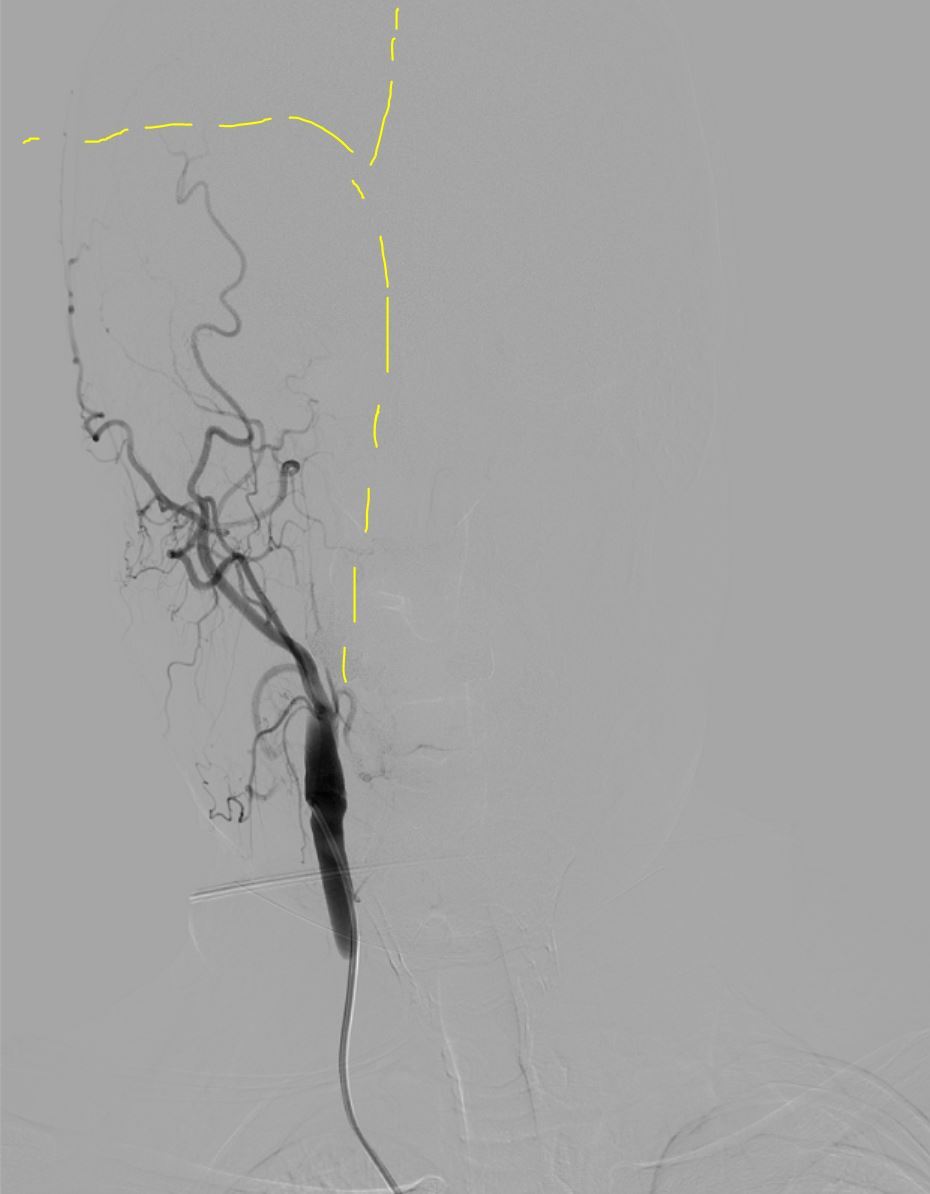

Далее гайд катетер вместо диагностики, с учетом характера поражения решаю выполнить комбинированную методику = аспирационный катетер с одновременным использованием стента ретривера (усиленная методика ВСТЭ, я ее предпочитаю). Делаю т.н. "матрешку" = в гайд аспирационник, далее микрокатетер и проводник для реканализации и заведения "микрика". Все получилось без особых усилий. После заведения микрокатетера провел стент ретривер (для извлечения тромба), раскрыл его, удалив микрик, заякорился и максимально, как мог подвел на аспирации аспирационный катетер (картинка ниже)

Далее делаю аспирацию с ретривером, дважды - минимальный прогресс, удалось только немного открыть ВСА:

Результат после двух попыток...